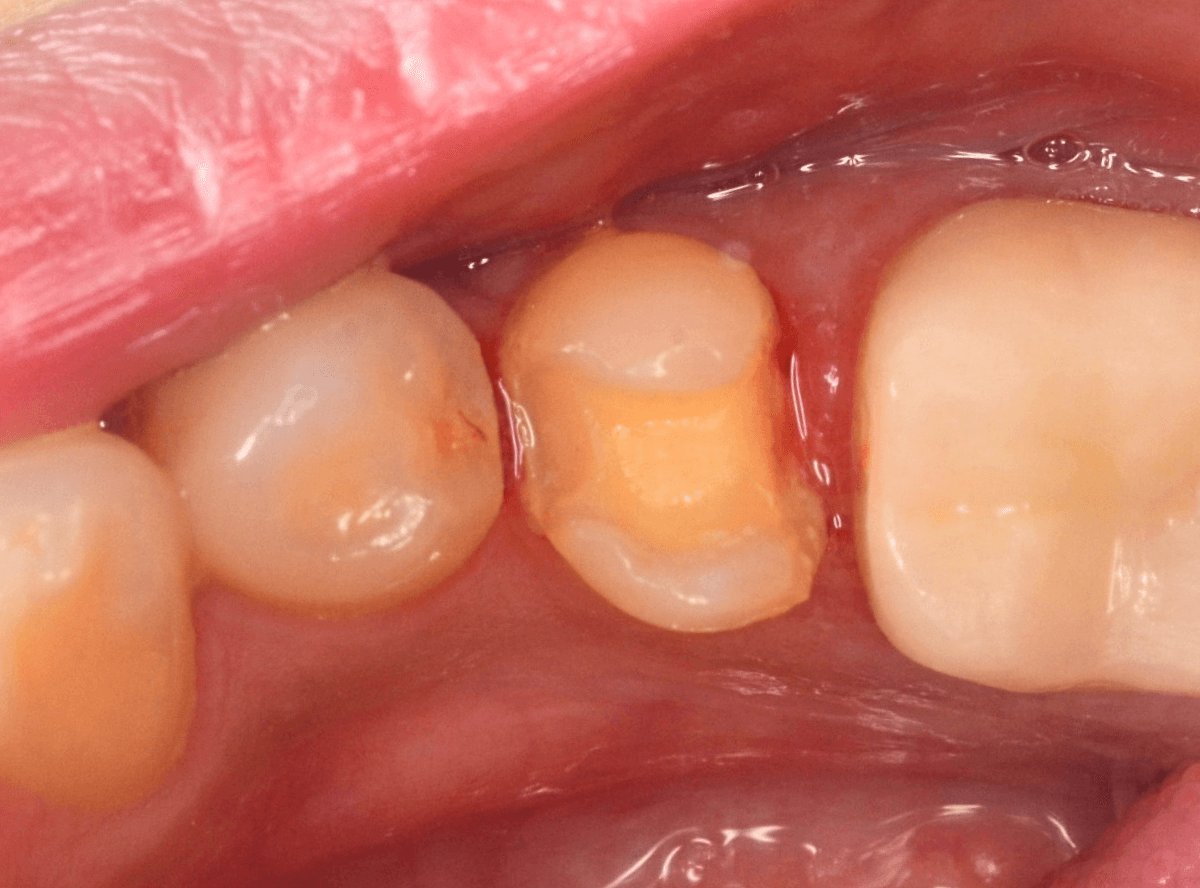

虫歯の治療を開始します。

隣の歯とのすき間を中心に広い虫歯になっていました。

虫歯治療後、特に症状もなく経過観察できましたので、つめものを作る治療に入ります。